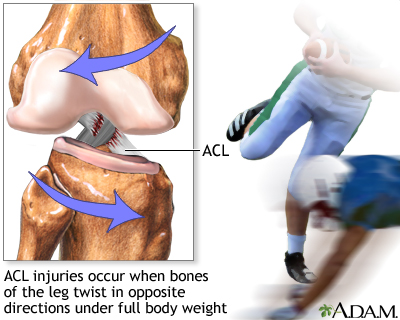

An ACL injury can occur if you:

- Get hit very hard on the side of your knee, such as during a football tackle

- Overextend your knee joint

- Quickly stop moving and change direction while running, landing from a jump, or turning

Basketball, football, soccer, and skiing are common sports linked to ACL tears.

ACL injuries often occur with other injuries. For example, an ACL tear often occurs along with tears to the MCL and the shock-absorbing cartilage in the knee (meniscus).

Most ACL tears occur in the middle of the ligament, or the ligament is pulled off the thigh bone. These injuries form a gap between the torn edges, and do not heal on their own.